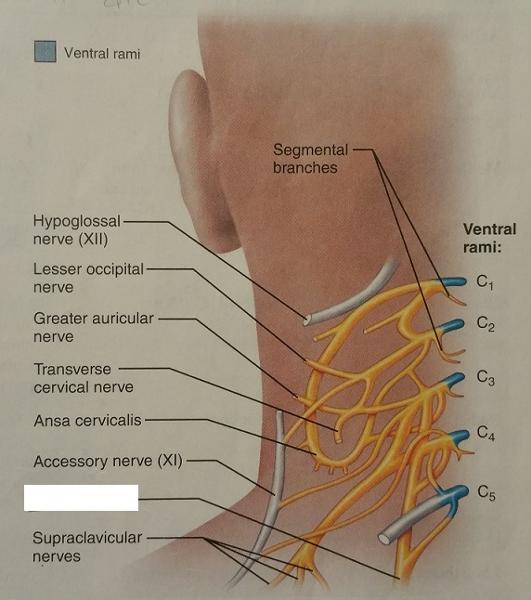

The cervical plexus arises from the ventral rami of what cervical nerves?

C1-C5

The cervical plexus supplies muscles of which 2 body parts?

1. Shoulder

2. Neck

What is the major motor branch (nerve) of the cervical plexus?

Phrenic nerve

The phrenic nerve arises from the ventral rami of which cervical nerves?

C3-C5

The phrenic nerve innervates which body part?

Diaphragm

What is the primary danger of a broken neck (in regard to which nerve being damaged)?

The phrenic nerve may be severed

If the phrenic nerve is severed, what 2 dangerous conditions could occur?

1. Paralysis of the diaphragm

2. Cessation of breathing